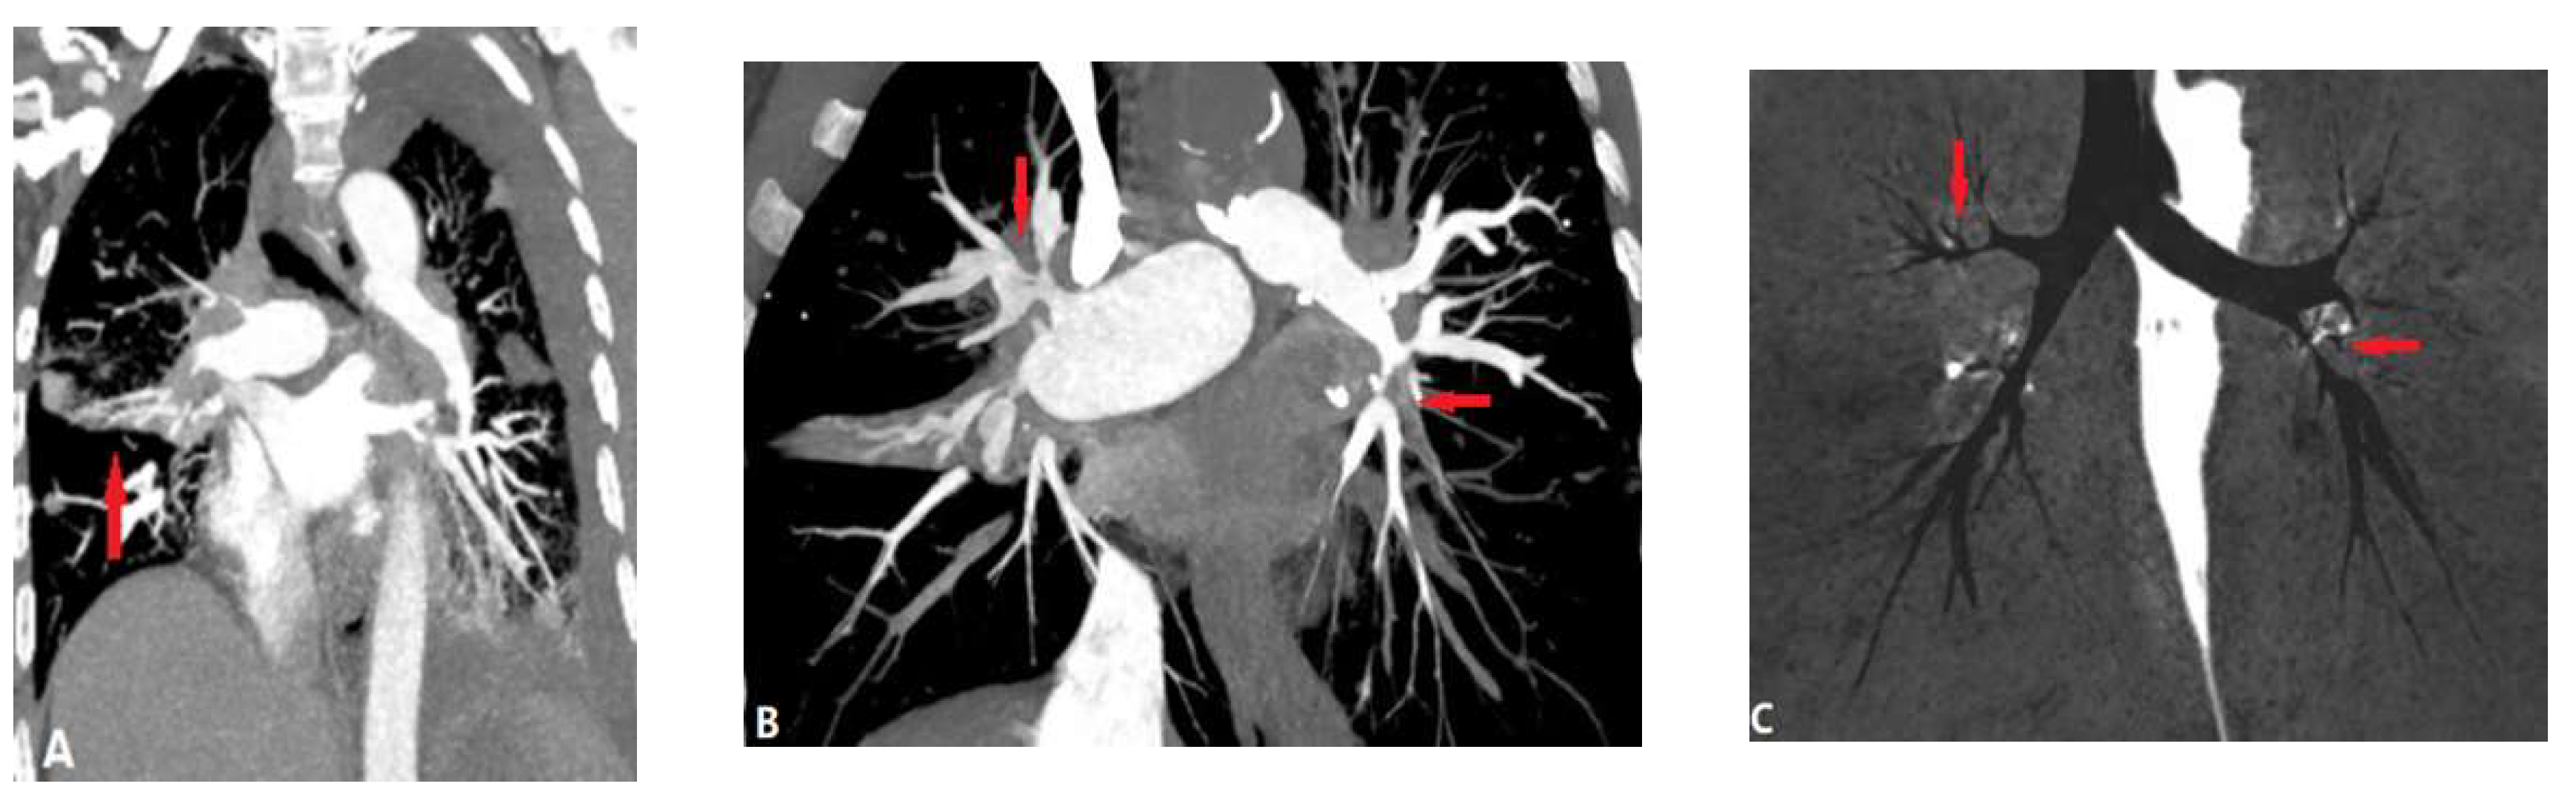

3.2.1.1. Takayasu Arteritis (TA)

3.2.1.2. Behçet Disease (BD)

3.3.1. Fibrosis Mediastinitis (FM)